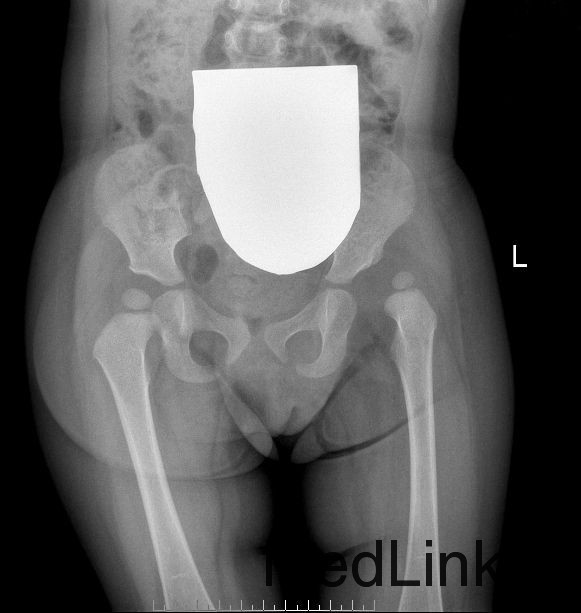

专科检查:抱入病房,行走跛行步态。双侧大腿皮纹不对称,左侧皮纹位置稍高。左下肢轻度外旋,左髋、膝关节轻度屈曲,左髋部无明显肿胀,无压痛、叩击痛,左髋关节外展稍受限,主动伸屈活动尚可,左大转子较对侧上移,Aills征(+),左下肢较对侧短缩约0.6cm,左下肢皮肤感觉正常,末梢血液循环好,各足趾活动良好。 骨盆正位片 :左侧发育性髋关节脱位:左侧髋臼角增大,左侧股骨头向外上移位,骨骺发育较对侧小,股骨头骨骺位于Perkins方格外上象限,Shenton氏线欠连续。髋臼指数:左侧37°,右侧23°。